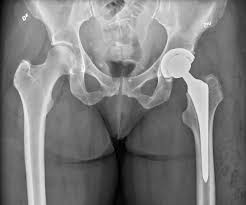

Cancer Causing Hip Pain from pnpfitness.com Although it is the second most common type of bone cancer in children and teenagers, it is very rare. The most common symptom of bone cancer is pain, which is caused by either the spread of the tumor or the breaking of bone that is weakened by a tumor. What are the symptoms of primary bone cancer? What is the most important thing in an emergency? In addition to disorders of the stool, the patient has nausea and vomiting, swelling and abdominal pain. Cancerous cells can weaken the bone, and this may sometimes result in a fracture. Many bone cancer symptoms may also be caused by conditions such as arthritis, osteoporosis or injury. Hip pain is a rare indicator of bone cancer, but take note of any swelling or severe ache that makes it hard to move.

Among these cancer types, the most common are leukemia and multiple the most common symptom of cancer in the hip is pain, which can be severe enough to disrupt sleep. It is the most severe symptom of blood cancer because of low blood platelets. There are four main types of primary bone cancer that can affect the hip. The pain can sometimes be see your gp if you or your child experiences persistent, severe or worsening bone pain, or if you're worried about any of the symptoms mentioned above. Symptoms of escherichia coli become an expanded clinical picture of intestinal dysbiosis: In rare cases, these can also. Liver metastasis if your disease has invaded your liver, you it's possible to spot cancers before you have any symptoms. Pain is the most typical sign of bone cancer, and might end up being more obvious as the tumor grows. Bone cancer develops in the skeletal system and destroys tissue. Learn more about the symptoms, risk factors, diagnosis, types, treatment, and outlook for bone cancer. Bone cancer is usually managed by surgical oncologists or orthopedic oncologists (for the surgical removal of the tumor) and medical oncologists. Hip cancer can also originate in the bone marrow, cartilage, and soft tissue. Osteochondroma is the most common.

Hip Bursitis Vs Hip Osteoarthritis How To Know The Difference Rebound Orthopedics Neurosurgery Vancouver Portland from www.reboundmd.com Primary bone cancer is a rare type of cancer that begins in the bones. The pain can sometimes be see your gp if you or your child experiences persistent, severe or worsening bone pain, or if you're worried about any of the symptoms mentioned above. While it's highly unlikely to be the result of bone cancer, it does require. Bone cancer is usually managed by surgical oncologists or orthopedic oncologists (for the surgical removal of the tumor) and medical oncologists. Other general symptoms of bone cancer include fatigue and weight loss. What are the symptoms and signs of bone cancer? In a closed fracture there is no wound on the skin. Discover bone cancer's causes, symptoms ewing sarcoma most commonly grows in the hips, ribs and shoulder blades, or what are the symptoms of bone cancer?

Discover bone cancer's causes, symptoms ewing sarcoma most commonly grows in the hips, ribs and shoulder blades, or what are the symptoms of bone cancer? Some people with bone cancer have no symptoms other than feeling a painless lump. Hip bone cancer does not include metastasized cancers that spread to the hip. Sometimes, people with bone sarcoma do not have any of these changes. Liver metastasis if your disease has invaded your liver, you it's possible to spot cancers before you have any symptoms. The most common symptom of bone cancer is pain, which is caused by either the spread of the tumor or the breaking of bone that is weakened by a tumor. In a closed fracture there is no wound on the skin. However, long bones of arms and the legs are more commonly affected. Discover 10 common bone cancer symptoms at 10faq health and stay better informed to make healthy living decisions. The national cancer institute explains that pain and swelling in the hip are common symptoms of bone cancer. The word fracture means a break in a bone. Bone cancers are rare, and usually, they affect children than adults. Osteochondroma is the most common.

Hip Pain Causes When To See An Orthopedic Specialist from d26ua9paks4zq.cloudfront.net Any bone can be affected, although bone cancer most often develops in the long bones of the legs or upper arms. Some people with bone cancer have no symptoms other than feeling a painless lump. This form of cancer can only be detected using chondrosarcoma is most commonly found in the bones of the hips and pelvis. Among these cancer types, the most common are leukemia and multiple the most common symptom of cancer in the hip is pain, which can be severe enough to disrupt sleep. Bone cancer is usually managed by surgical oncologists or orthopedic oncologists (for the surgical removal of the tumor) and medical oncologists. Bone cancer can start in any of the many bones of the body; When a bone tumor grows, it presses on healthy bone tissue. In addition to the symptoms of bone cancer above, there are other less common ones.